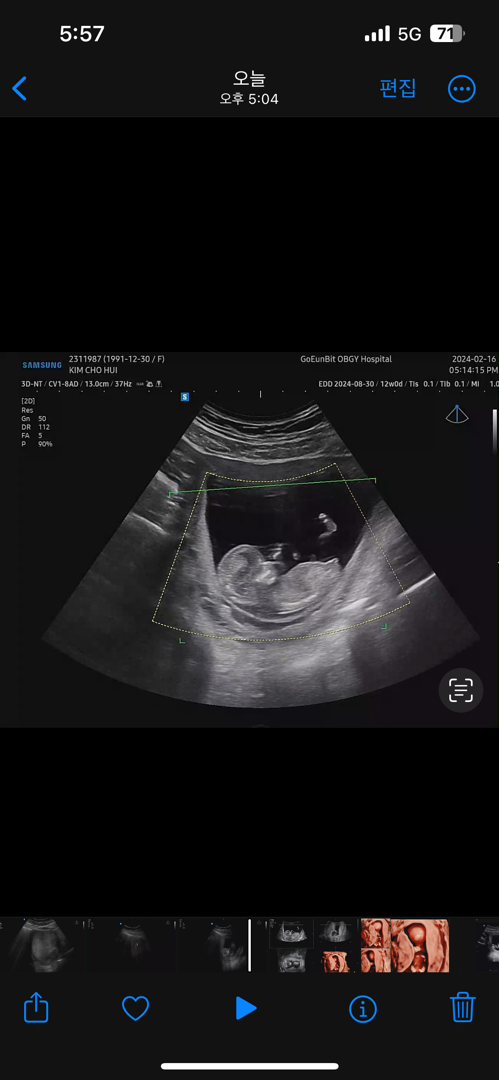

신행가기전에 알고가고싶어요ㅠ3ㅠ 12주 고수분들 봐주세욤♥️

저저번주 다른병원에서는 다리 사이 매끈하댔는데 오늘은 읭..? 하구 모르겠더라구요 힌트도 안주시고ㅠㅠ 저 부분으로 유추하는게 맞는진 모르겠는데 한번씩 봐주고 가셔요♥️